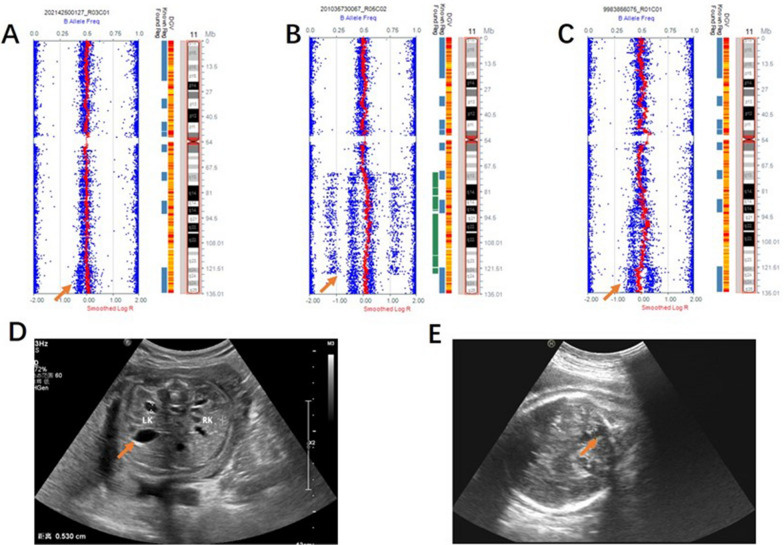

Fig. 1.

SNP array results and mechanisms for mosaic trisomy 16. The log R ratio indicates an increase in copy number, between two and three copies. Additional shifts in the B allele frequency are observed, corresponding to a shift in B allele frequency from 0% towards 33% (in the case of AA in the euploid cell line and AAB in the trisomic cell line), and a shift from 100% toward 66% (in the case of BB in the euploid cell line and ABB in the trisomic cell line). The additional haplotypes are visible near the centromere, consistent with a meiosis I nondisjunction. The crossovers were in 16p12.3 and 16q22.1, indicating that these loci were hot spot of recombination. A Mosaic trisomy 16 in case 5 arose from meiosis I with the presence of five visible crossovers. The proportion of cells exhibiting mosaic trisomy 16 was 20%. B Mosaic trisomy 16 in case 6 arose from meiosis I with 3 crossovers. The proportion of cells exhibiting mosaic trisomy 16 was 30%. C Mosaic trisomy 16 of case 7 arose from meiosis I with 4 crossovers. The proportion of cells exhibiting mosaic trisomy 16 was 20%

Fig. 6.

SNP array and ultrasound malformations of mosaic 11q segmental duplication. A Case 41 arose by mitotic non-disjunction with mosaic duplication of 11q23.3q25. B Case 42 arose by meiotic I non-disjunction with mosaic duplication of 11q13.4q25. C Case 43 arose by mitotic non-disjunction with mosaic duplication of 11q14.3q24.1 combined with mosaic deletion of 11q24.1q25. D Enlarged pelvis malformation was observed on ultrasound for case 41. E The ultrasound malformation of case 42 was a posterior cranial fossa communicating with the lateral ventricle